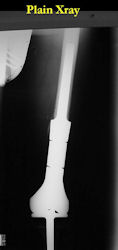

| Limb-sparing surgery for osteosarcoma of distal femur – Plain Xrays |

In each case, the tumor and bone from which it arose were resected. This required meticulous dissection, mobilization and preservation of adjacent pertinent neurovascular structures. In each case presented here, the defect was reconstructed with a special modular segmental tumor prosthesis. This also replaces the adjacent joint in many instances.

Examples of radical limb sparing surgeries for osteosarcomas in various anatomic locations (distal femur, proximal tibia, proximal humerus, scapula)